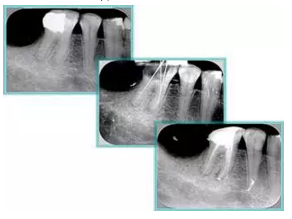

6. 鈣化

常見有修復(fù)性鈣化和增齡性鈣化。下面為根管鈣化 X 線片。

7. 器械折斷

右圖及下圖為器械折斷的 X 線片。箭頭處示折斷器械。

右圖箭頭處示臺階形成。